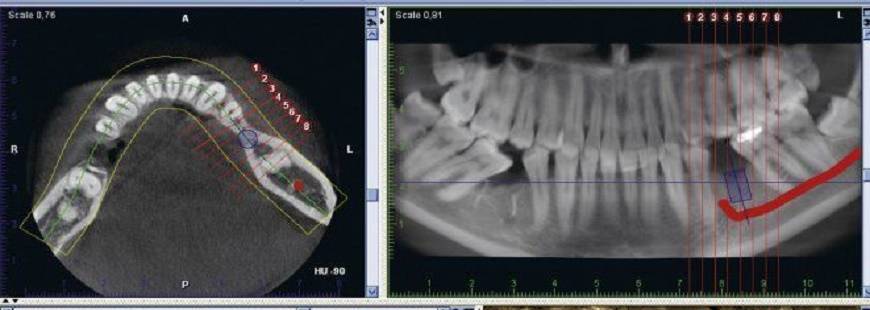

Pacjenci mogą się tez poddać badaniom tomografem komputerowym. Badania TK obejmują okolicę zęba, szczękę, żuchwę, zatoki szczękowe.